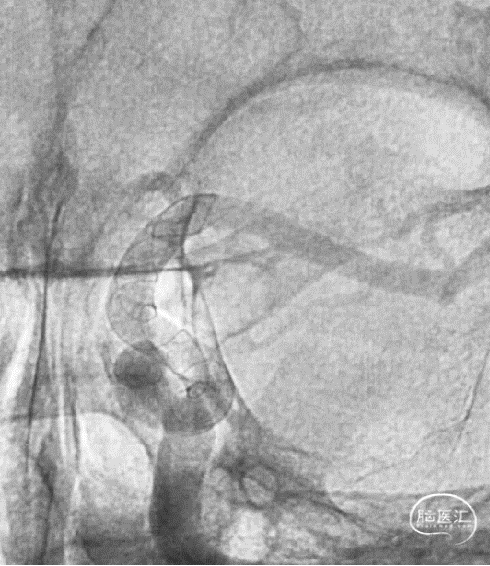

现病史:患者因头痛17天,外院行头颅CTA提示:左侧颈内动脉交通段动脉瘤,动脉瘤大小约5.3×5.4mm,形态不规则,左侧大脑前动脉A1段瘤样凸起。

术前影像学资料

头颅CTA

可见一小泡自动脉瘤瘤体上发出

瘤体最大径6.92mm

远端血管直径:3.28mm

近端血管直径:3.98mm

同侧A1可见一小瘤突起